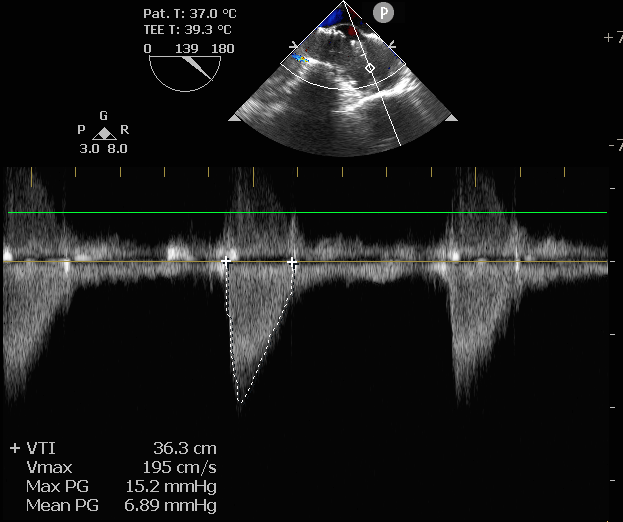

术后即刻评估

术后压差从78.3mmHg降至6.89mmHg,瓣膜正常工作,患者血流动力学即刻得到改善。